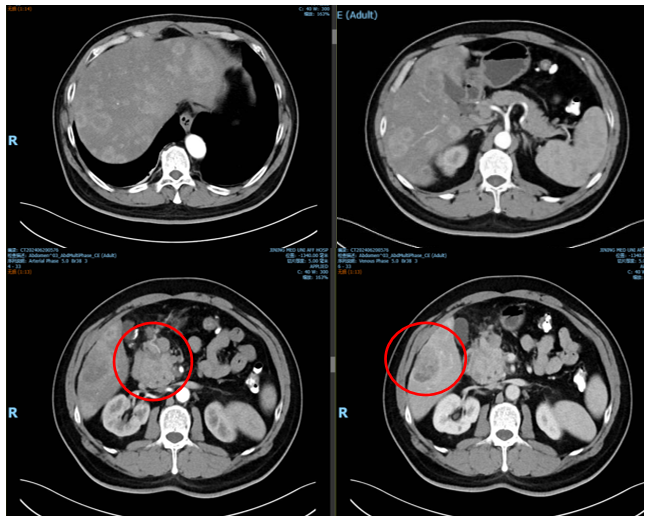

2024年6月20日行腹部强化CT检查提示:肝内多发占位性病变,考虑转移瘤可能大;胰头部占位性病变伴周围淋巴结增大,考虑恶性,胰腺癌或恶性胰腺神经内分泌瘤可能大(图3)。

2024年6月18日行超声引导下肝占位穿刺活检,病理提示:查见呈片状及巢状异型增生的上皮细胞伴坏死,符合神经内分泌瘤(NET:G2)。免疫组化:CD56(+),CgA(+),Syn(+),SSTR2(3+),CD10(-),CD34(-),Hepatocyte(-),GPC-3(-),Beta-catenin细胞核(-),INSM1(+),insulin(-),P53(野生型表达)RB1(+),Ki-67(+,局部约3%)。

初步诊断:胰腺神经内分泌瘤伴肝转移(cT3N1M1a Ⅳ期)。